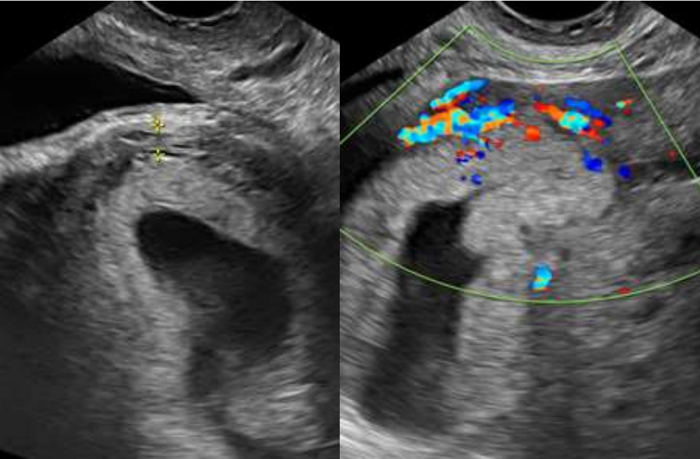

Paciente, 32 anos, secundigesta (cesariana anterior), na 6ª semana de gravidez com queixa de sangramento genital há 20 dias, com piora há 12 horas. Ao exame encontrava-se com estado geral bom, hipocorada (+/4+), acianótica, consciente e orientada. Pressão arterial de 120 x 80 mmHg. Frequência cardíaca de 98 bpm. Abdome plano depressível e indolor, sem massas palpáveis e ausência de sinais de irritação peritoneal.

Submetida a exame ultrassonográfico transvaginal com a imagem abaixo, revelando saco gestacional dentro de cavidade uterina, de contorno regular, em topografia de istmocele.